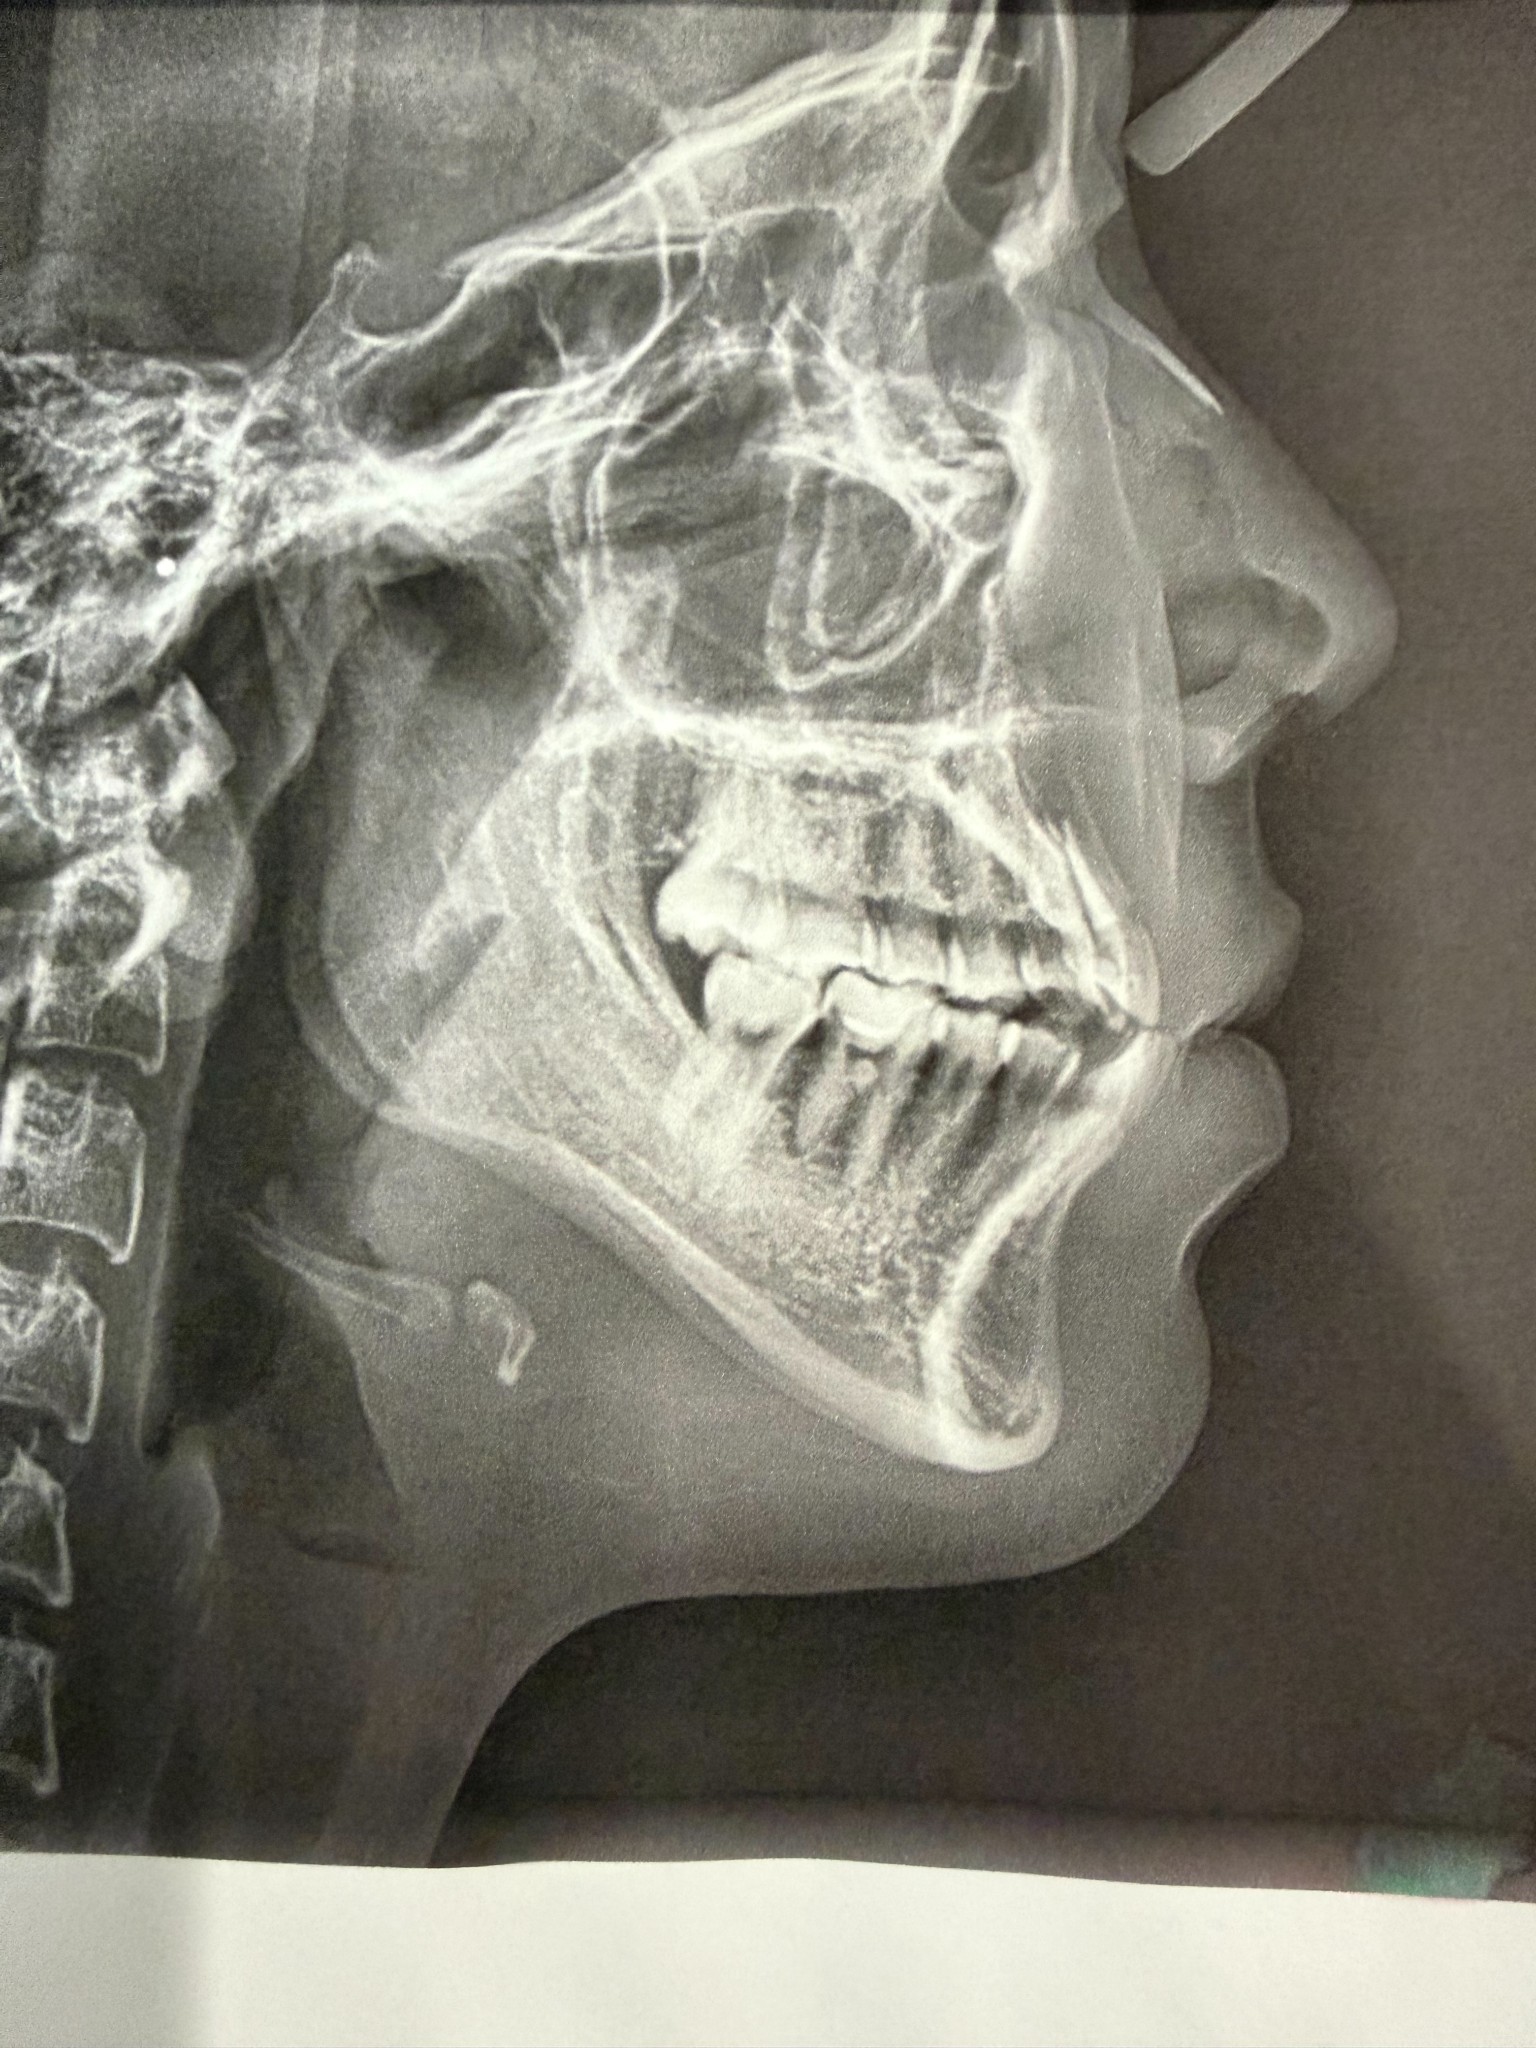

ขอสอบถามค่ะ พอดีเรามีปัญหารากฟัน ฟันล่างยื่นออกมา และอื่นๆตามภาพฟิล์มเลยค่ะ เคยไปสอบถามคลินิค เขาบอกว่าเป็นงานยากส่วนใหญ่ไม่รับเลย ให้ไปที่โรงพยาบาล เราไม่ทราบรายละเอียดเลย ปกติโรงพยาบาลจัดฟันได้ด้วยหรอคะ แล้วปกติส่วนมากจะไปที่โรงพยาบาลไหนกัน สอบถามผู้รุ้หน่อยค่ะ